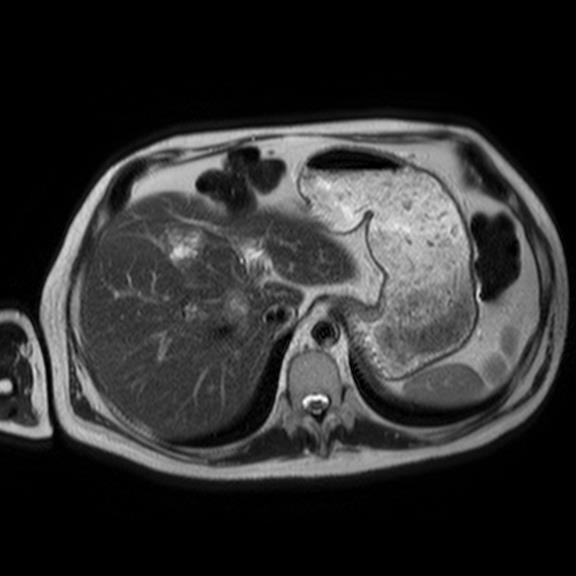

Nearly 11 months after his initial presentation, the patient presented again to his doctor for another follow up. At that point it was clear that the patient was declining rapidly. The rash had spread to his perineum and groin. He described the rash as excruciatingly painful to the point where the patient needed a wheelchair to ambulate. Upon further questioning, the patient reported a thirty pound weight loss over the prior 4 months. He still endorsed the diarrhea. A closer examination of his mouth and oral mucosa revealed dry, cracked and inflamed lips. The patient stated he had noticed this for about a year but did not make much of it. Lab work showed a new normocytic anemia with Hemoglobin of 11.4, an albumin of 2.8, and ESR of 63, and a blood sugar of 165. A malignancy work up was started at this point. CT of his abdomen revealed a pancreatic tail mass as well as three focal liver lesions which were confirmed on MRI (Figures 2-4).

Figure 4 Abdominal MRI showing focal hepatic lesions.